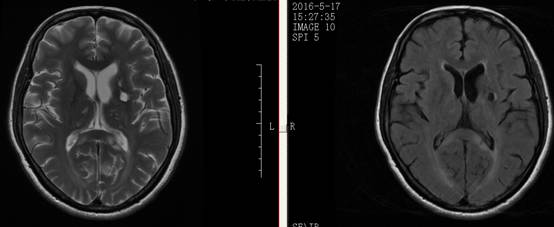

1周前,郭大姐再次发生右侧肢体无力的症状,于是家人将她送到广东三九脑科医院神经内科就诊,入院后积极完善相关检查,颅脑DWI显示:1、左侧基底节区、大脑脚及桥脑右侧、右侧枕叶多发陈旧性脑梗塞,2、考虑胼胝体压部偏左侧脑梗塞(偏慢性期)(如图1、图2)。DSA检查提示:1. 基底动脉末端闭塞,双侧大脑后动脉、后交通动脉未见显影,双侧大脑中动脉经皮层软膜动脉向同侧枕叶代偿供血;2. 双侧颈内动脉起始部重度狭窄(如图4、图5),狭窄率约90%,狭窄长度约20px;3.双侧椎动脉起始部中度狭窄,狭窄率约50%;4. 脑动脉硬化,颅内动脉走行僵硬,呈不同程度狭窄。

图 1 术前MRI提示:左侧基底节区、大脑脚及桥脑右侧、右侧枕叶多发陈旧性脑梗塞;

图 2 术前MRI提示:左侧基底节区、大脑脚及桥脑右侧、右侧枕叶多发陈旧性脑梗塞;